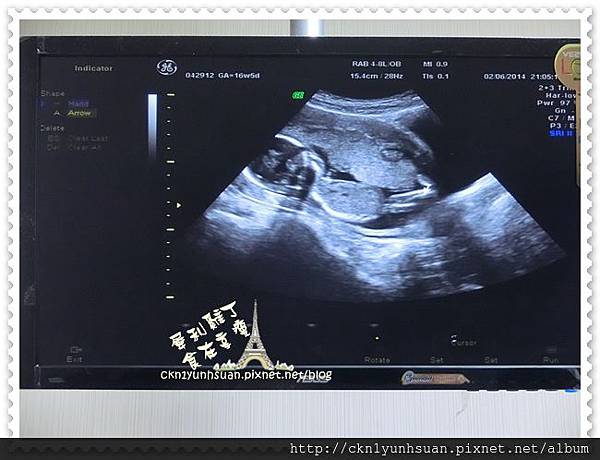

16W5D,媽咪55.7KG BMI:22.2

這小子是不是非常非常蘇湖的躺在他媽咪的懷裡~~~

雙手抱著他大大的頭,腳腳還舒服地交叉著

悠閒愜意的呢~口可~媽咪的可愛寶貝

醫生叔叔說你應該是個男寶寶!

可是因為兩隻大腿中間的突出物還太小…所以還不敢斷定